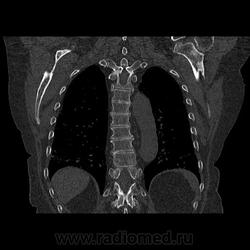

Женщина, 64 года. Жалобы на увеличение в размере левой верхней конечности. До 1999 года в больнице не была. В 1999 году поставлен диагноз туберкулома правого легкого без признаков активности процесса. Далее на ежегодных флюорограммах без динамики. В 2003 году мастэктомия. В декабре 2011 года повышение онкомаркеров - не обратила внимания, не консультировалась. Флюорография в феврале 2012 года -заключение туберкулома правого легкого, в остальном без патологии. В июне отметила увеличение верхней левой конечности. Повторно сдала на маркеры - уровень значительно повышен. Онколог направил на Р-гр ОГК, УЗИ брюшной полости, УЗИ молочных желез. По УЗИ в зоне послеоперационного рубца узловые образования - взята биопсия. По рентгену в заключении написал Р-картина легочного канцероматозного лимфангита, двусторонний гидроторакс, осумкованный интерлобарный междолевой гидроторакс справа, Р-картина множественного метастатического поражения костей плечевого пояса, грудной клетки. Рекомендовал КТ. Данные КТ заставили усомниться насчет лимфангоита и метастазов в кости. Может ли быть метастатический процесс настолько распространенным? Больше похоже на какой-то "пятнистый остеосклероз". За лимфангит тоже данных нет - перибронховаскулярный, междольковый интерстиций не утолщены, без узелков. А по реннтгену очень похоже на интерстициальные изменения. Отложил заключение до понедельника.

///Может ли быть метастатический процесс настолько распространенным? Больше похоже на какой-то "пятнистый остеосклероз"./// - не сомневайтесь, коллега, может. Вот Sclerotic breast cancer metastasizes in the pelvis http://en.wikipedia.org/wiki/File:ScleroticMets.PNG А "пятнистый остеопороз" - термин, вполне себе, мифический.

Диффузное поражение костей, смешанное (литическое и бластическое) - вероятно мтс. Менее вероятны при таком анамнезе болезнь Педжета, гиперпаратиреоз... Интересный случай тут: http://www.healio.com/endocrinology/bone-mineral-metabolism/news/print/endocrine-today/%7BF1AE5CCA-C96D-4E6E-8678-CAB36537EEDD%7D/A-complicated-case-of-Pagets-disease-of-the-bone

Выпот и отек руки, а так же изменения переднего средостения в верхнем этаже + кости + анамнез = вероятность метастазирования высока.